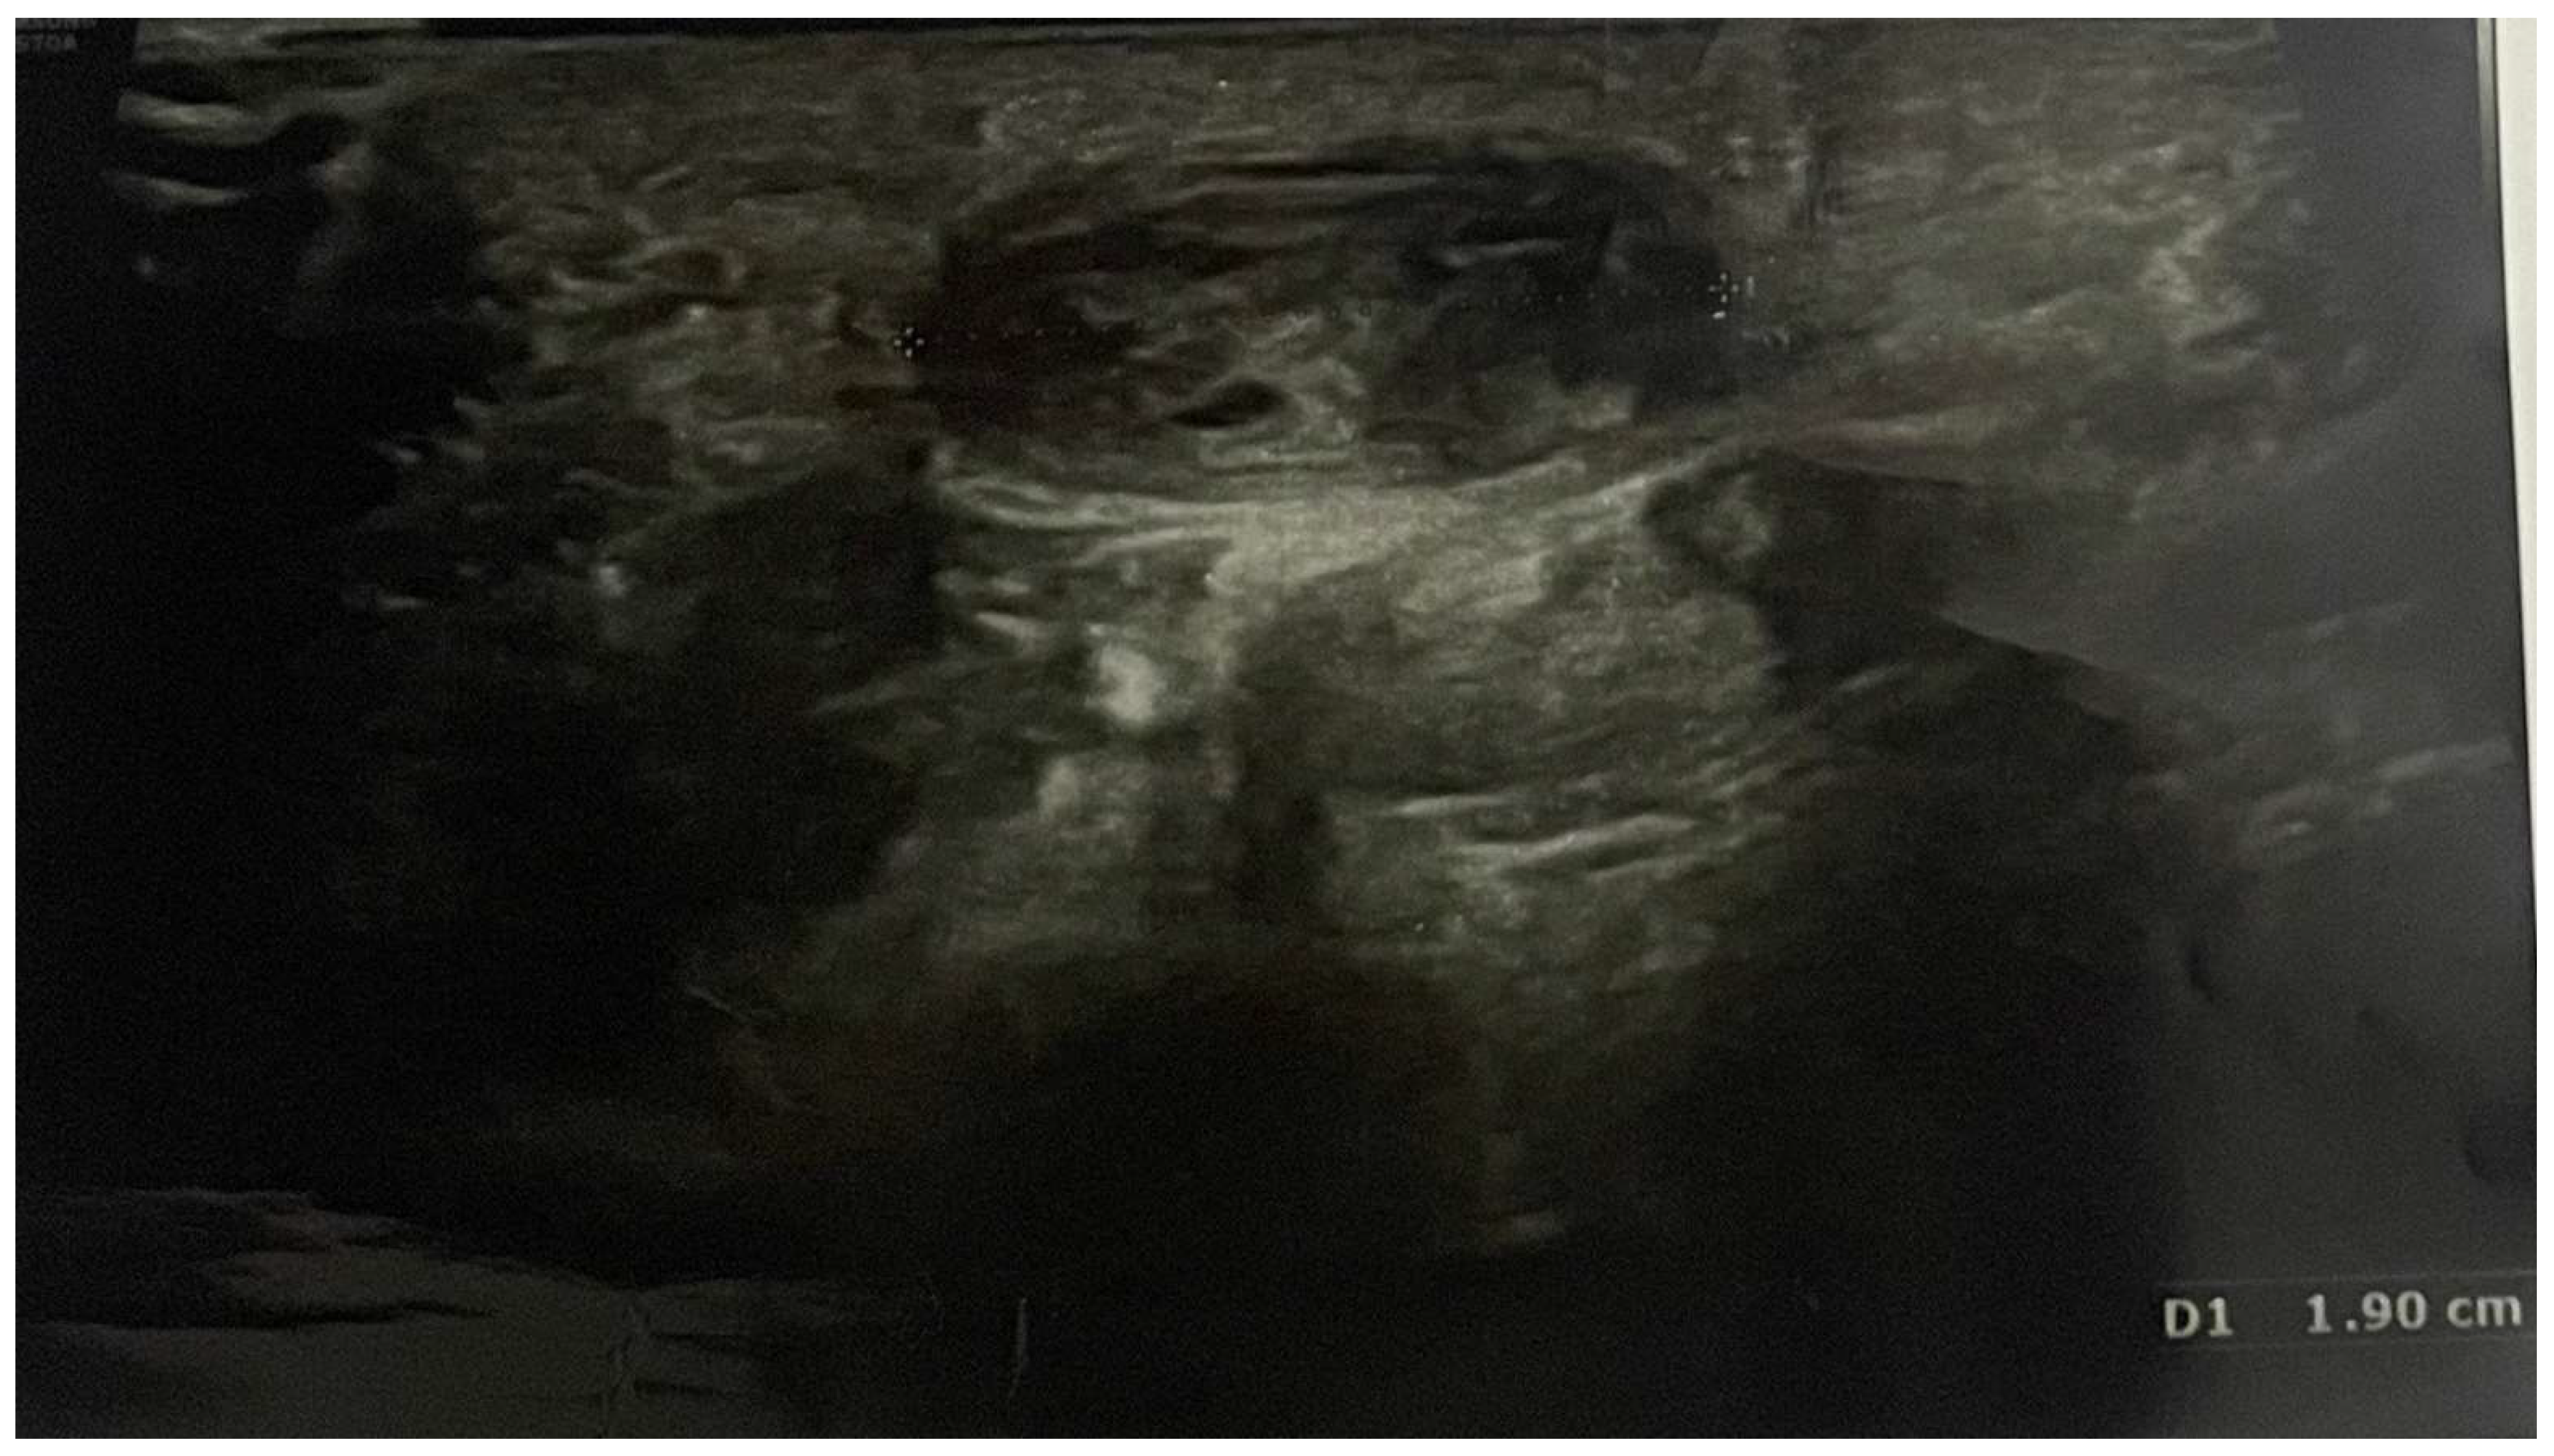

Pain, discomfort, and paraesthesia were present for over 1.5 years. Ultrasound imaging allowed for the diagnosis of an ulnar artery aneurysm of approximately 19 mm (Figure 1).

Figure 1. Preoperative ultrasonography; D1 shows the length of ulnar artery aneurysm (19 mm).